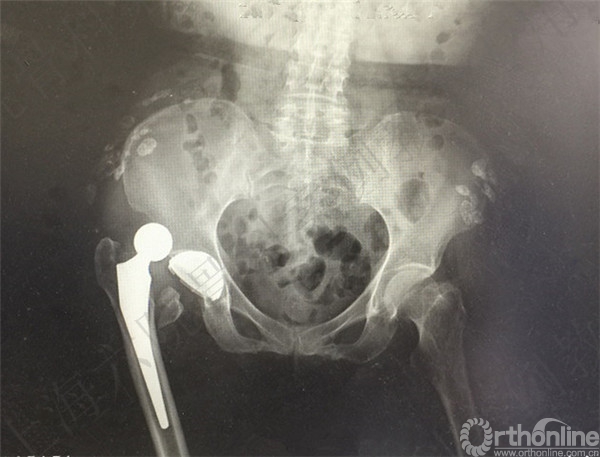

患者2周后自行下地摔倒至右髋假体周围骨折,假体松动,择期行长柄假体置换术+假体周围骨折切开复位内固定术。